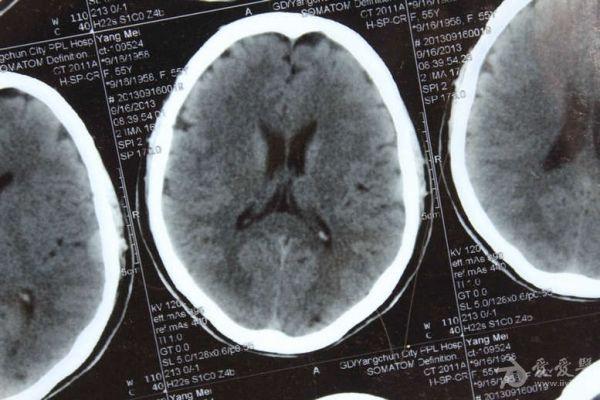

脑部占位病变CT,MRI图片,请帮忙诊断

最近感图样,无其它脑病病史

考虑脑膜瘤!!

磁共振没有平扫,增强矢状位没找到病灶。像脑膜瘤。

图片不是很清楚,应该是脑膜瘤!